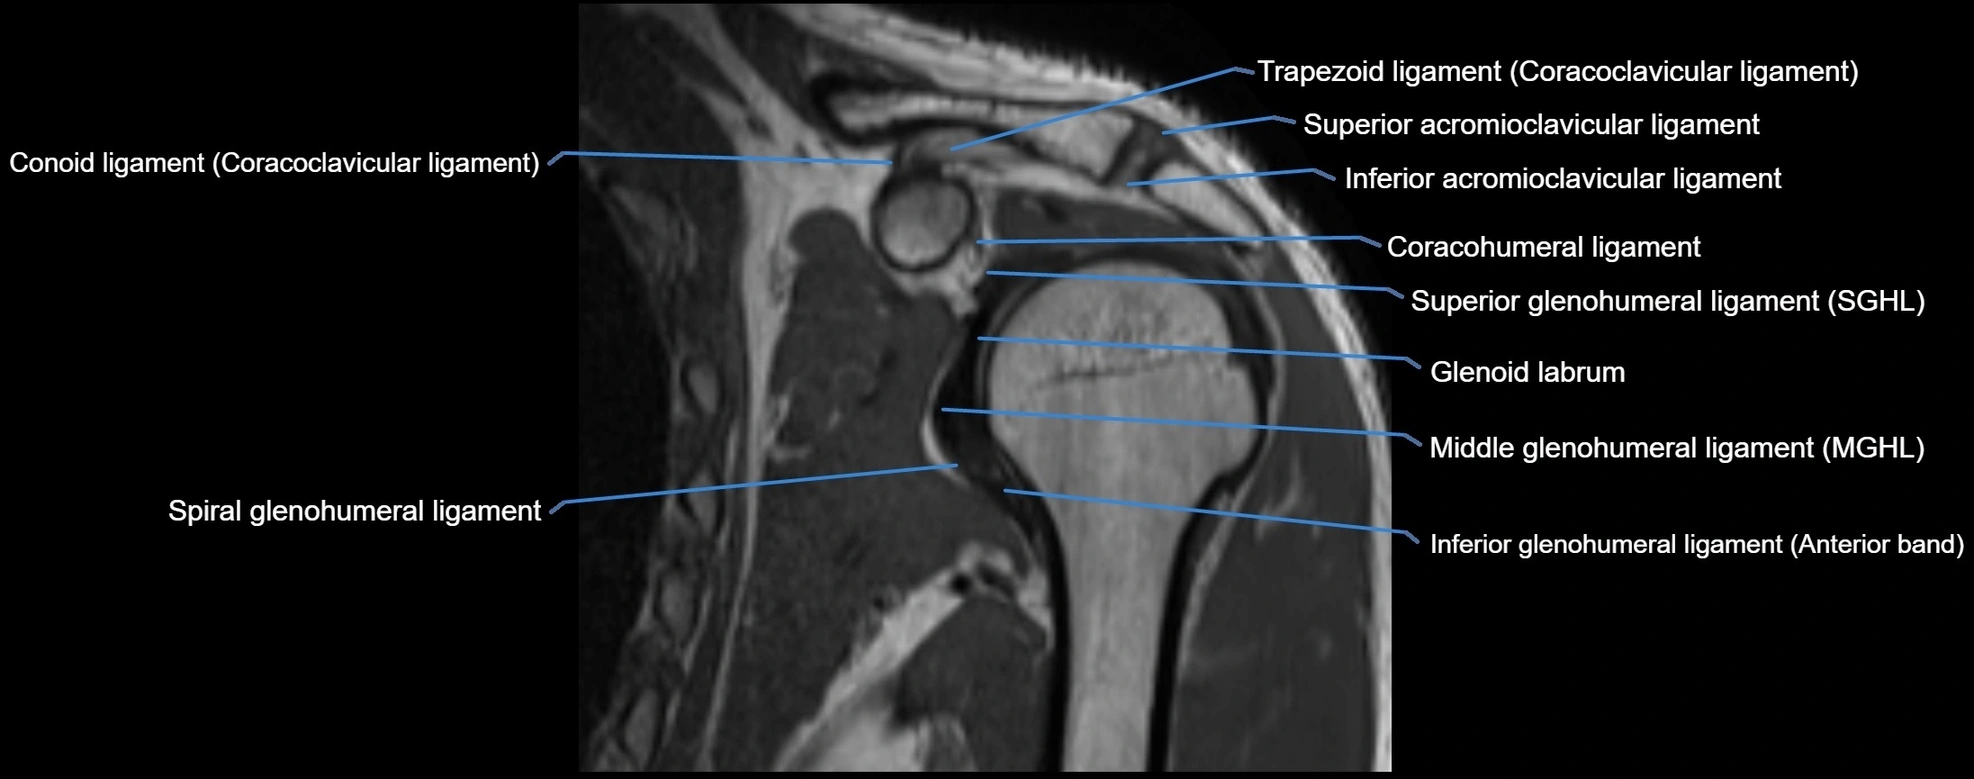

MRI images

image